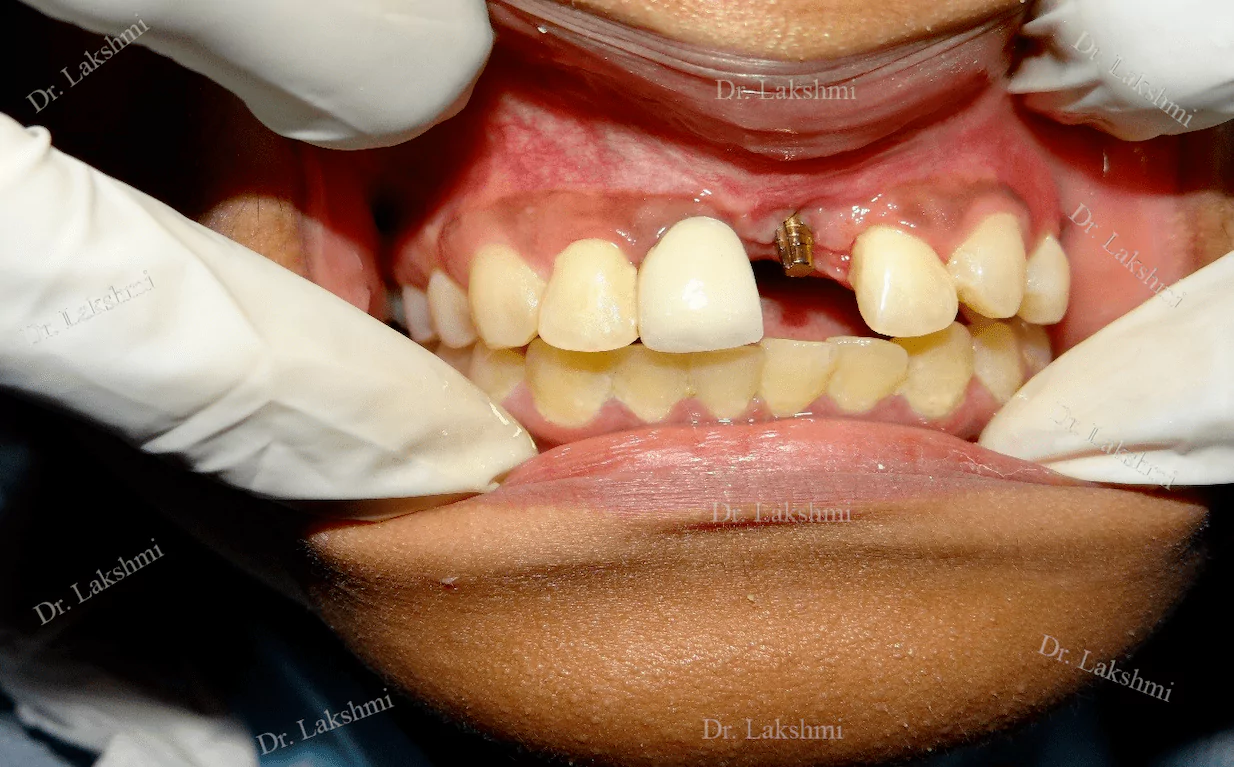

Dental implants have come to define modern dentistry in the last few decades. Dental implants are cemented to the jawbone and an abutment is used as a support for the dental crown that is placed over it. There are a single piece, two-piece and three-piece abutments available for implants. Titanium fuses naturally with the jawbone and that makes it a perfect fit as an implant. There are several dental implant techniques available to opt from, for a patient. The freedom to opt also depends on the condition of the jawbone and the gum.

Requires the placement of a single dental implant (either 2 stage or 1 stage) in the region of the missing tooth, followed by a crown (artificial tooth) over

Treatment Duration: 2 stage dental implants: The replacement is completed in 2 stages which are spread over an interval of minimum 3 months. The first stage involves the placement of the implant and requires one to two sittings,Temporary Crowns will be given to the patient. The second stage involves the placement of the artificial tooth (Permanent crown).